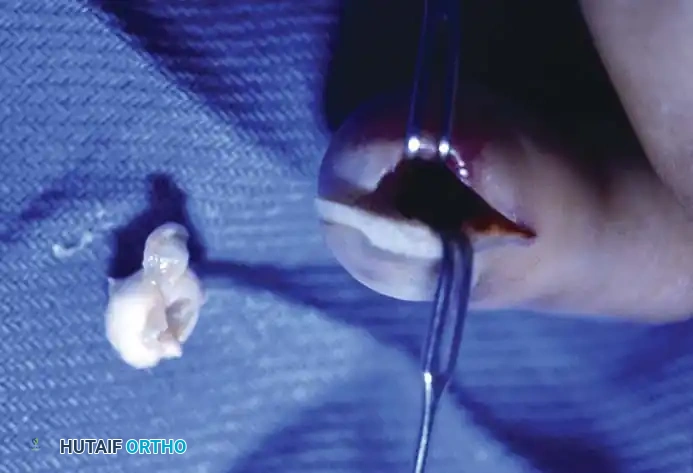

- Stalk Excision: Using a combination of sharp and blunt dissection, mobilize the ganglion in its entirety. Trace the stalk down to its capsular origin at the dorsal scapholunate ligament. Excise the cyst along with a 1-cm margin of the dorsal capsule. Do not excise the substance of the scapholunate interosseous ligament itself, as this will cause carpal instability.

Excision of the ganglion stalk along with a generous margin of the dorsal joint capsule.

- Neurectomy: Identify the terminal sensory fibers of the posterior interosseous nerve (PIN) at the floor of the fourth compartment. Divide the nerve and gently cauterize the proximal end to denervate the dorsal capsule and reduce postoperative pain.

Cauterization of the capsular margins and the terminal branches of the posterior interosseous nerve.